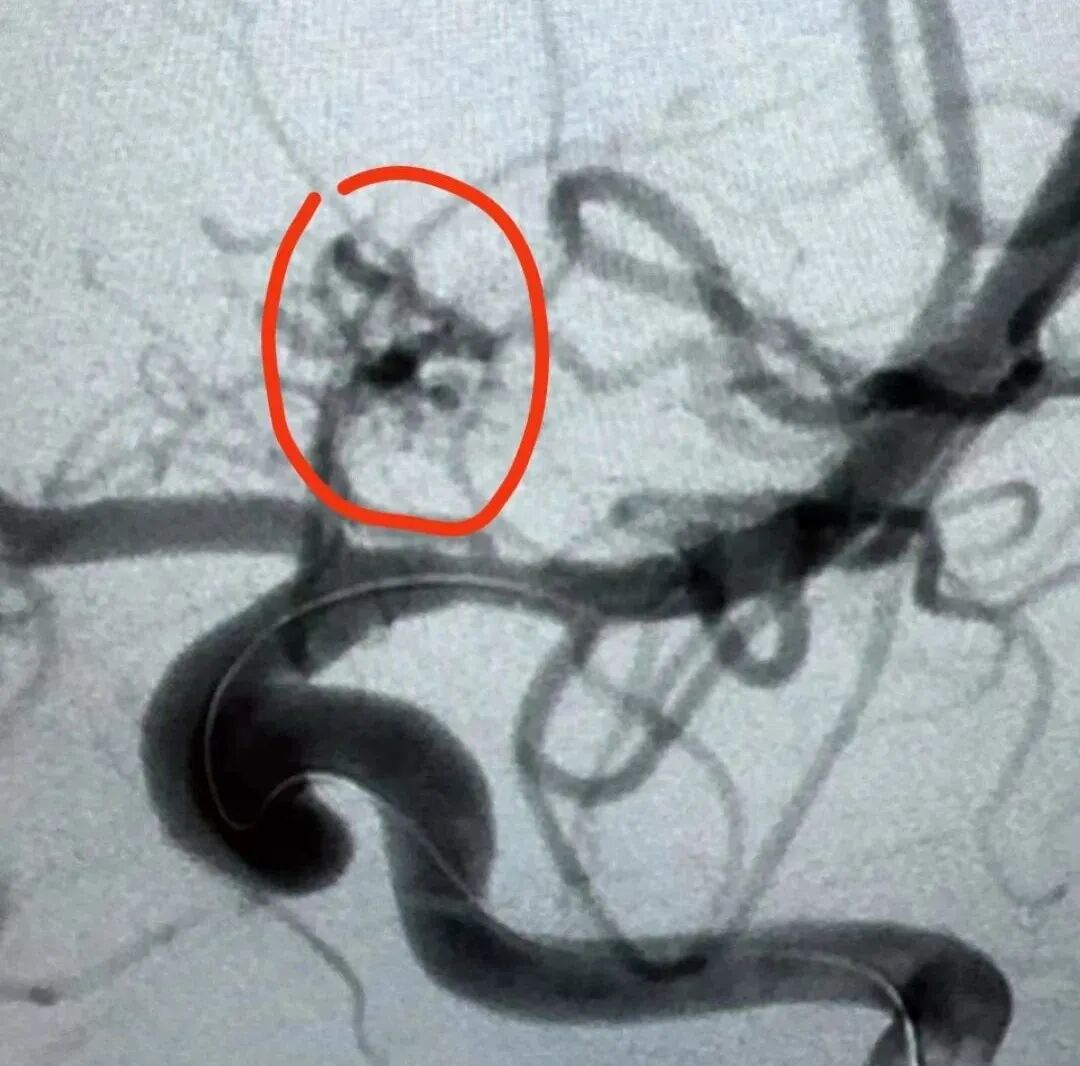

最終,小霖經(jīng)腦卒中綠色通道,迅速完成術(shù)前準(zhǔn)備并送入介入室。在與介入室、急診科、麻醉科的通力合作下,神經(jīng)外科血管組景英朝團(tuán)隊(duì)歷時2個小時,順利完成手術(shù),小霖的腦血管畸形被順利栓塞,手術(shù)獲得圓滿成功。

術(shù)前腦血管畸形團(tuán)消失

術(shù)后,通過醫(yī)護(hù)人員的精心治療和護(hù)理,小霖的肢體無力癥狀已經(jīng)消失,目前康復(fù)良好,已出院返校。